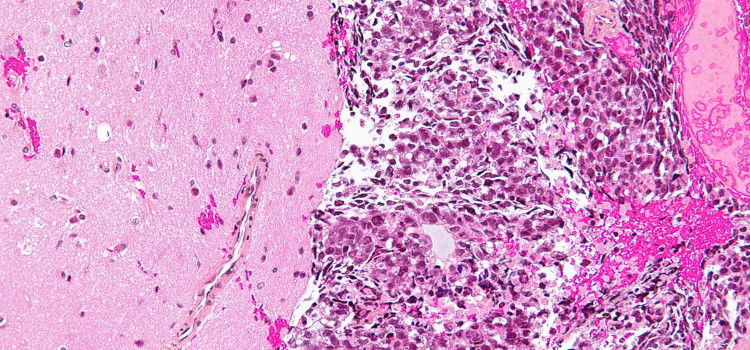

Un fármaco para el cáncer busca frenar al Covid-19 20.04.2020 El ensayo español Copérnico estudia si una inmunoterapia contra tumores de mama o pulmón es eficaz en pacientes graves que no responden al tratamiento estándar